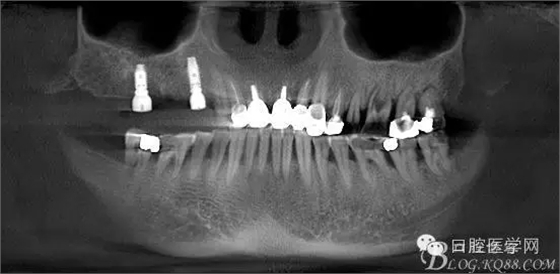

這是初診時候的CT片截圖。目標(biāo)是14到16固定橋,別的牙齒先慢慢來,那么牙周肯定要做的,哪怕我要把14 16拔了,我也必須先去牙周科刮治。 在這里我感謝我們醫(yī)院的牙周科所有同事幫我們很多。刮治以后的牙齒拔掉即刻種植相對沒刮治過的牙齒肉芽會少很多,那么我在手術(shù)時候速度會快,會省力很多,我最討厭去刮很多肉芽,有時候搔刮肉芽的時間和精力比種牙的兩倍還多 而且很多肉芽會增加種植手術(shù)風(fēng)險和術(shù)后反應(yīng)最主要手術(shù)可以行云流水患者感覺良好 (我們一般會牙周治療和等待一段時間再約種植手術(shù))者。

上圖14牙位和16牙位是我們想植入種植體的位置,考慮到47牙位還存在且沒有要拔掉的意思,那么我設(shè)計植體的時候適當(dāng)往17牙位靠點。